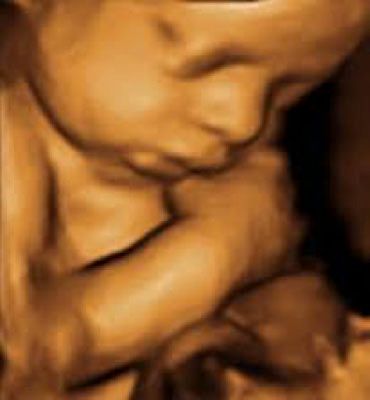

Prenatal Testing

Prenatal Testing (NIPT)

Chorion villus sampling (CVS)

Amniocentesis